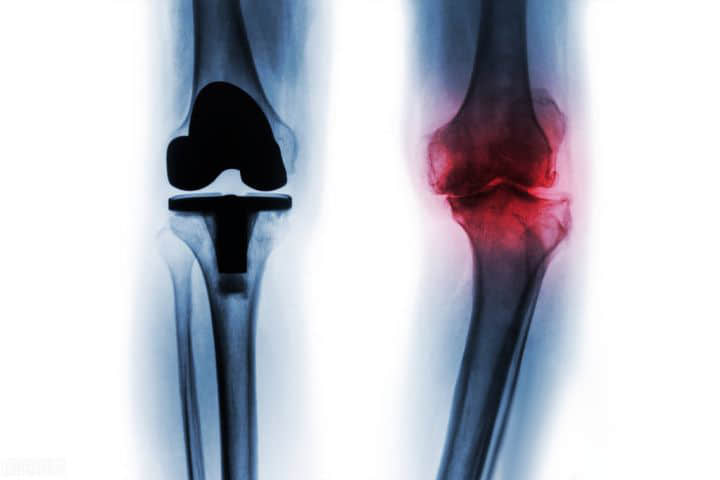

下面就让我们来认识一下人工膝关节假体。目前人工膝关节是由钴铬钼合金和高交联的超高分子聚乙烯制造,经久耐用。根据使用部位不同,膝关节假体可分为单体假体、双体假体及三间室(全膝)假体。根据固定方式,可以分为骨水泥固定假体和非骨水泥(生物)固定假体。根据假体设计的限制程度,可以分为非限制性假体、部分限制性假体、高限制性假体和全限制性假体。

1、股骨假体:放置于股骨远端的股骨假体,由金属合金组成;

2、胫骨假体:可以是高交联聚乙烯的单一假体设计,也可以是两部分组件的组合式设计,由金属托和高交联聚乙烯垫片组成,垫片在金属托上固定或滑动;

3、胫骨假体:安置于颅骨的残留骨床上,与股骨假体之间构成髌股关节面,一般由高交联聚乙烯组成。